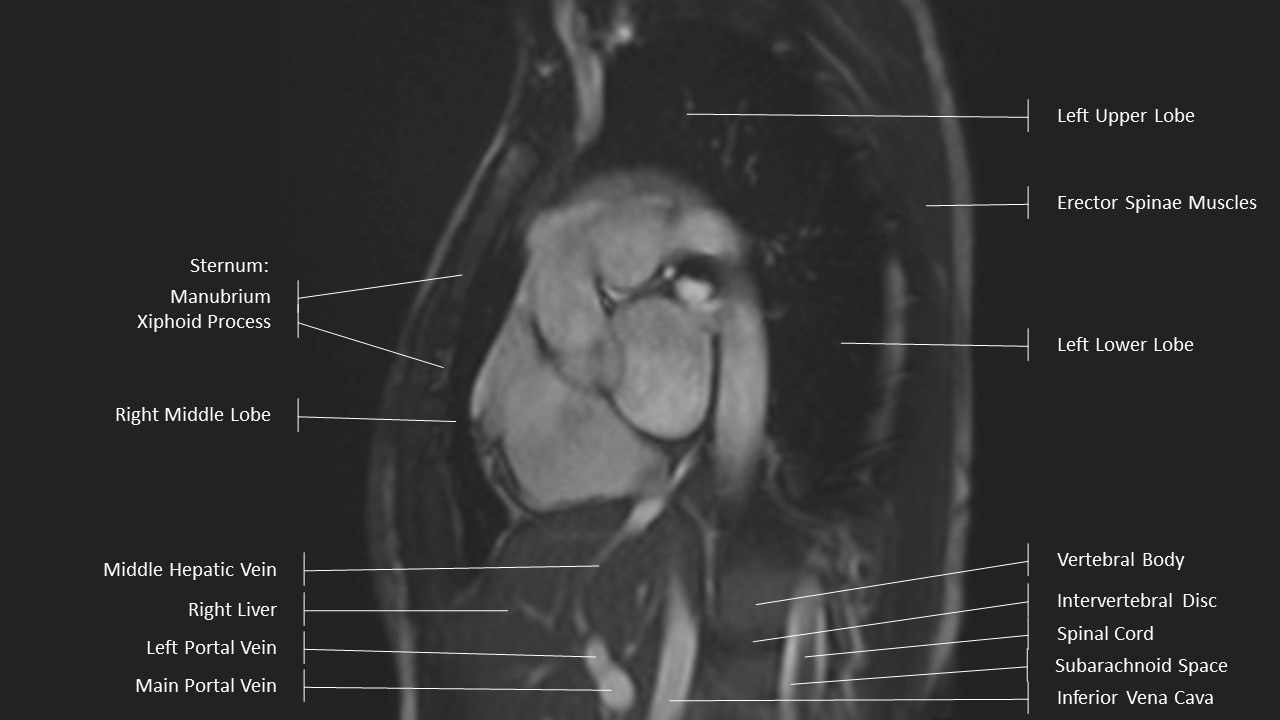

Aortic Arch Series